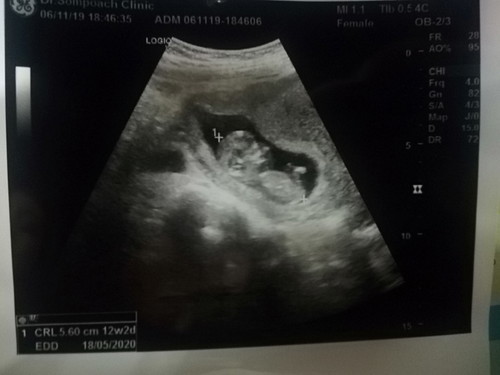

12สัปดาห์

คาดว่าน่าจะไม่ถึง12สัปดาห์แต่ขนาดของหนูโตเร็วเกินเพราะหมอเลื่อนกำหนดคลอดเข้ามาอีกแล้วตอนนับประมาน11wโตเร็วเกินไปดีมั้ยคะ

น้ำหนักตามเกณฑก็ดีค่ะ